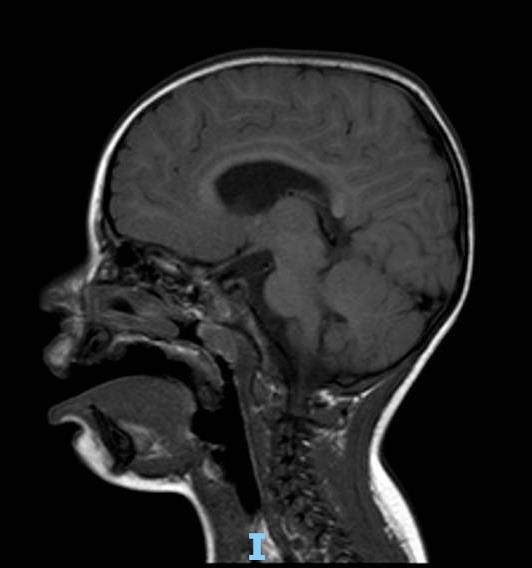

- Outcomes of periventricular leukomalacia

- Diagnosis: SPASTIC DIPLEGIA as a result of Cerebral Palsy, with increased tone in distal areas

• Neuromotor profile consistent with spastic diplegia